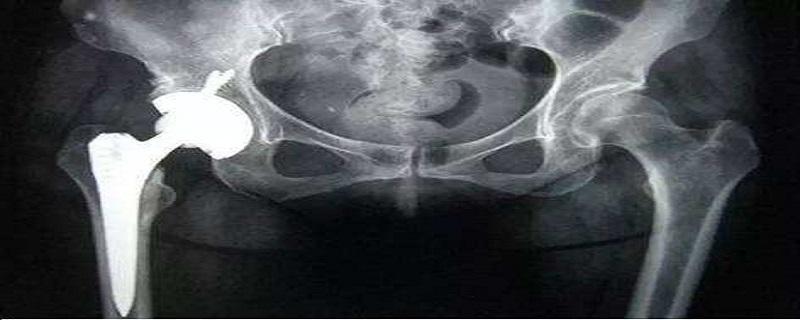

髋关节置换有叫做人工髋关节置换,主要是将包含股骨和髋臼的假体,用骨水泥和螺丝钉固定在正常骨质上,来取代病变关节,那么髋关节置换选择什么材料呢?

两类是指一类是放在髋臼侧的,这个是有一个臼杯,是放在外面的,直接放在髋臼里面,臼杯里面还需要放一个内衬。 第二,股骨侧的,股骨侧通常也是两部分组成,首先是有一个假体柄,这个假体柄通常都是金属的,有的是钴铬钼合金的,有的是钛合金的,现在一般都是上面带一层涂层。 然后就是人工股骨头,这个人工股骨头最开始是个大头,后来随着临床进展和科学技术的发展,现在变成小头,它也分不同的型号。

髋关节置换术实际置换的是两部分,一部分是髋臼的部分,一部分是股骨。 髋臼的部分目前金属的通常都用螺丝钉固定一枚到两枚,所以髋臼这个部分基本上是不会松动。容易发生松动的是股骨假体的部分,股骨假体部分主要是跟骨水泥技术有关,以前是一代二代骨水泥,它有它自身的缺陷,比如里面的泡沫比较多,而且搅拌也不是特别均匀。 现在是变成第四代骨水泥技术,最新的骨水泥技术搅拌更加均匀,骨水泥的固化时间更加缩短,而且还发明了真空技术,在真空下进行完基本上没有气泡,所以如果要是用这种骨水泥技术的话,髋关节股骨头假体松动的机会能降低不少。 另外一点,目前股骨假体应用骨水泥已经很少了,除非翻修的时候或者是在一些比较落后的地区。现在都用的是生物型假体,生物型假体上面有大孔和微孔,主要通过周围的组织长到微孔里面,然后跟股骨头产生固定。就像用无数的钢丝把两个东西绑到一块儿。 所以髋关节置换如果手术做了没有问题,术后也不要过度使用关节,尤其不要受伤,发生松动的机会不太大。